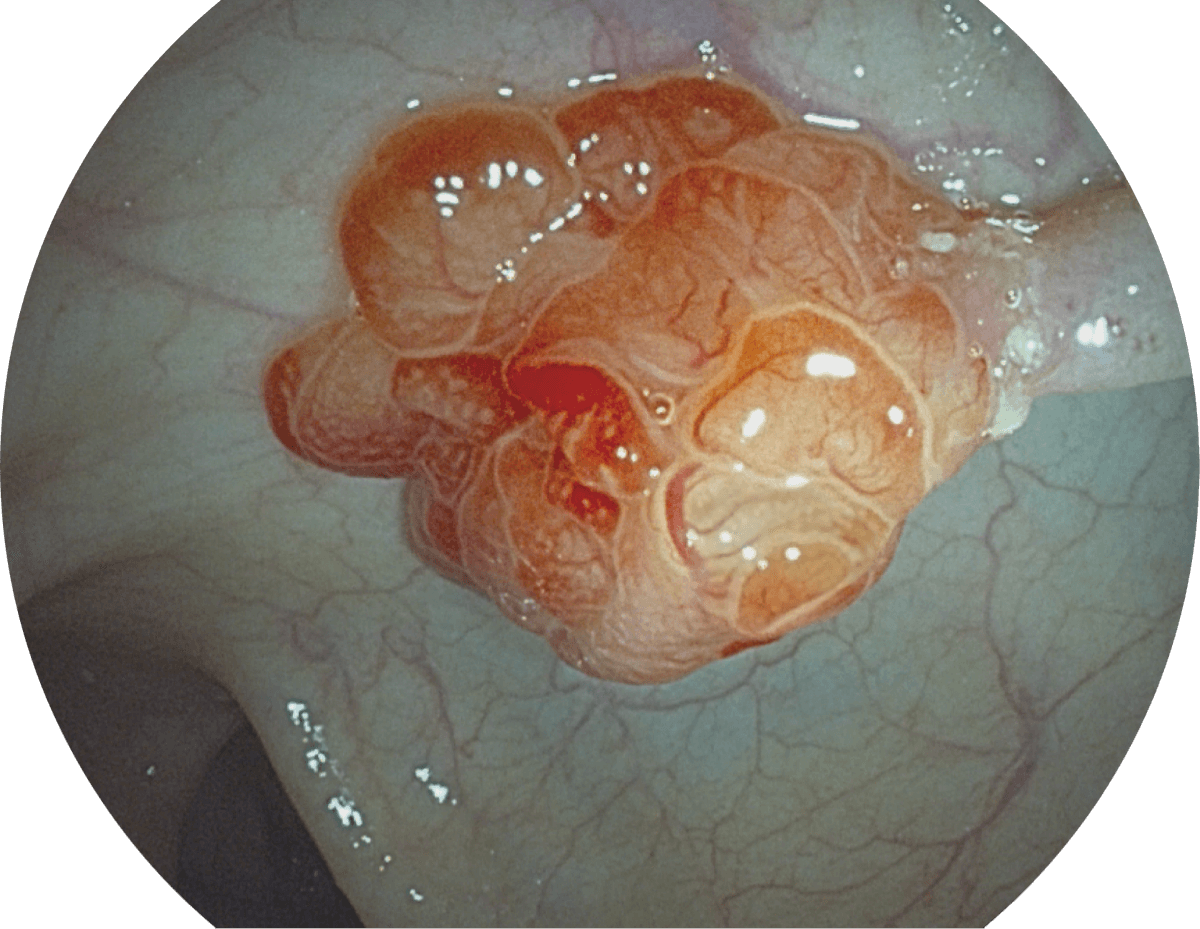

具有聚谱成像技术(SFI)及光电复合染色成像技术(VIST),可完美呈现粘膜细节及病变特征。

WL

SFI

VIST